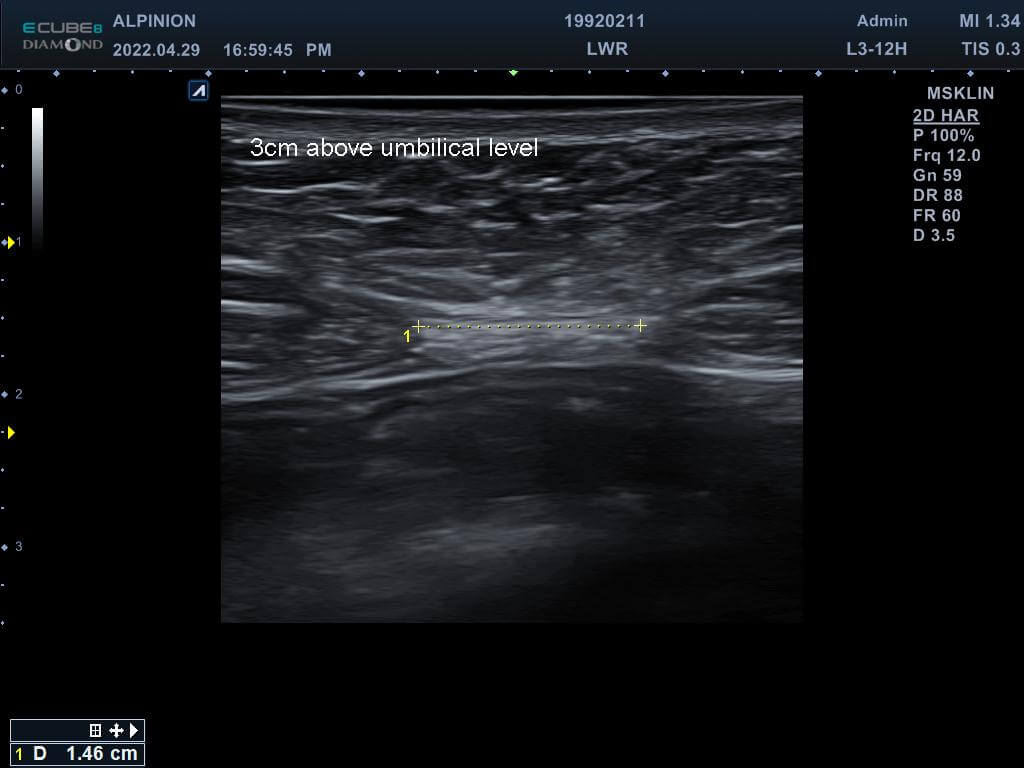

專業的醫師先在磁刺激前測量林小姐的腹直肌厚度,發現雙側的腹直肌分別為0.81cm(右側)與0.78cm(左側),同時雙側白線的距離也長達1.96cm,已經達到腹直肌分離的狀況。在使用了四周共8次的增肌減脂機後,雙側的腹直肌增厚為0.93cm(右側)與0.82cm(左側),同時雙側白線的距離減少1.46cm並明顯增厚,代表結締組織已經增生修復了。

使用(後)白線長度減少至1.46cm